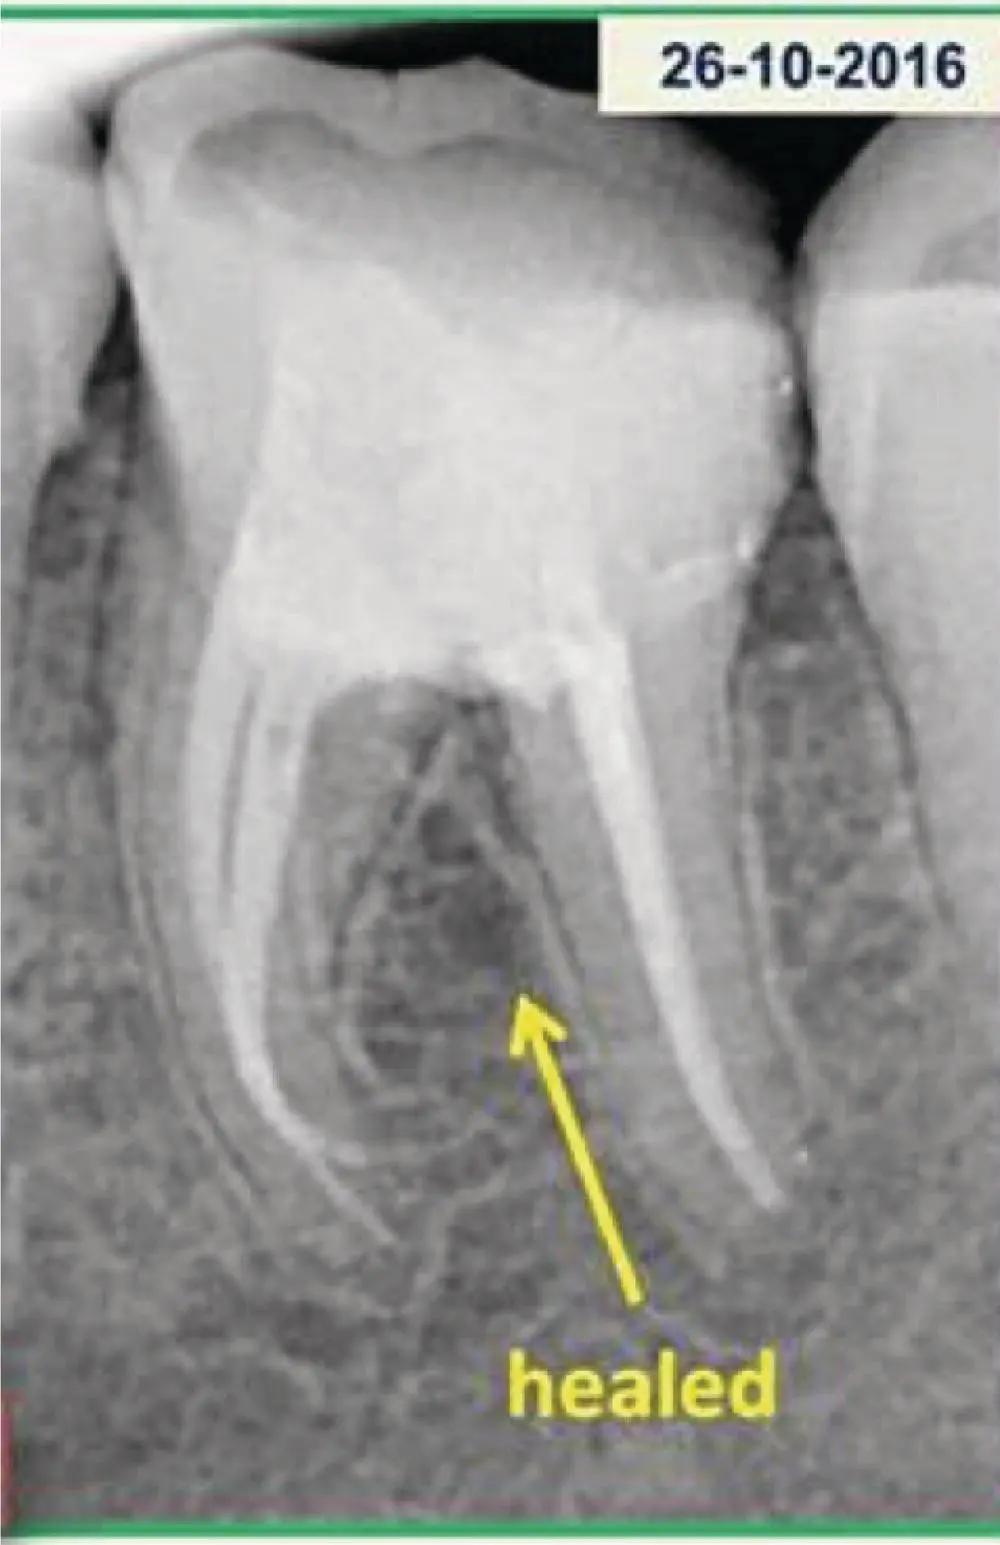

Follow for 2.5 years. The follow‐up radiograph shows formation of a bony trabecular pattern. Clinical and radiographic healing is evident on follow‐up visits ( Figure 1.6).

Figure 1.6 Follow‐up radiograph showing healing in the furcation area.